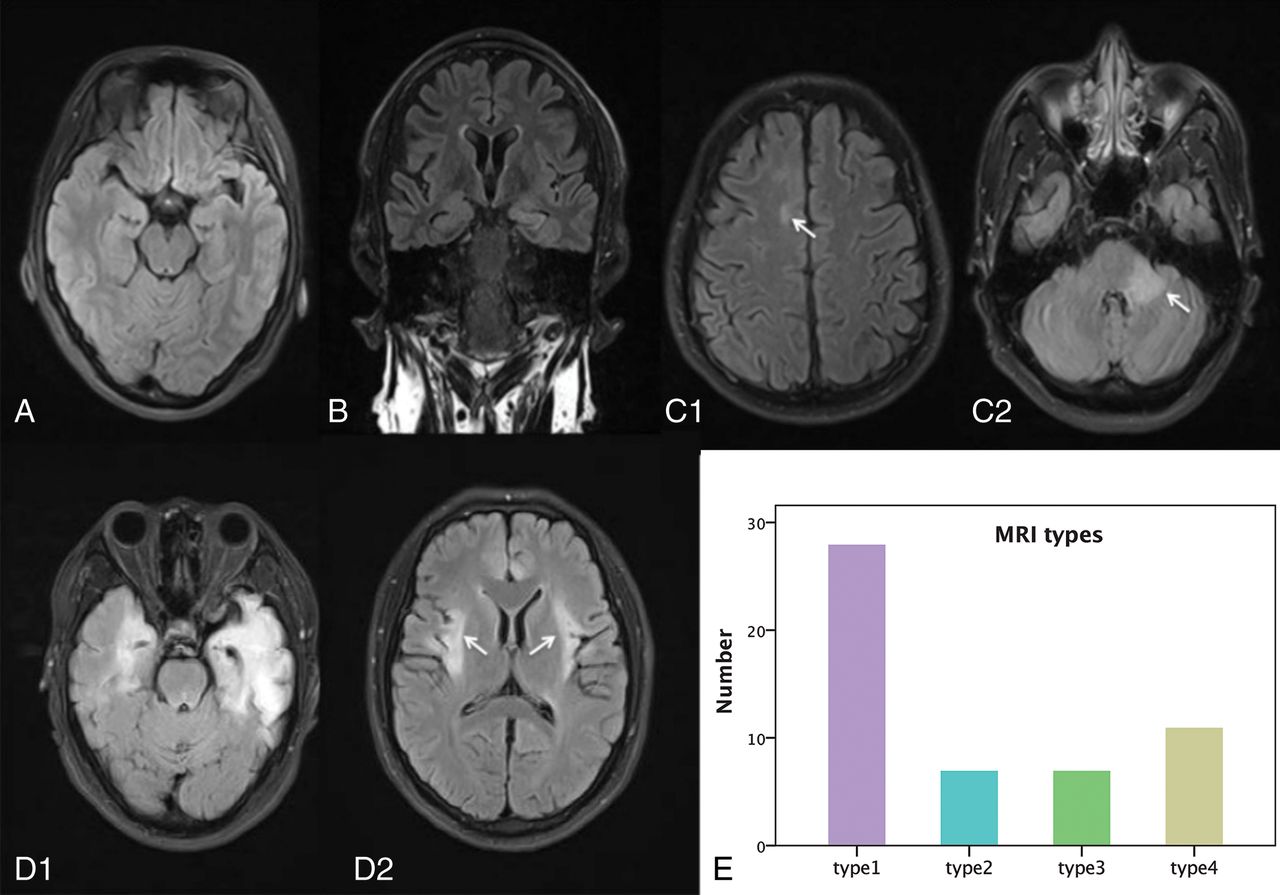

Twenty-eight (28/53, 53%) patients with anti-NMDA receptor encephalitis had normal MR imaging (type 1) results at the onset phase, and 25 patients (25/53; 47%) presented with abnormal MR imaging results—type 2: seven patients (7/25, 28%) with lesions in the hippocampus only; type 3: seven patients with lesions in the frontal lobe (n = 3); cingulate gyrus and middle cerebellar peduncle (n = 2); and corpus callosum, insula, basal ganglia, thalamus, and brain stem (n = 1), without hippocampal lesions; and type 4: 11 patients (11/25, 44%) with lesions in both the hippocampus and other brain areas, including the frontal lobe and temporal lobes (n = 8); parietal lobe (n = 5); thalamus (n = 3); basal ganglia, cingulate gyrus, and brain stem (n = 2); and insula, occipital lobe, corpus callosum, and internal capsule (n = 1). One patient had only limbic lesions among 18 patients in types 3 and 4. The sample images of the 4 MR imaging types are shown in Fig 1, and the lesion probability map is shown in Fig 2. Normal brain MR imaging results were observed more frequently in female patients (19 of 28, 68%) than in male patients (9 of 25, 36%) (P = .020). No difference was observed in brain MR imaging manifestations between age groups (pediatric versus adult groups) (P = .982).

Four types of brain MR imaging appearances in patients with anti-NMDA receptor encephalitis, and the histogram of the 4 types of brain MR imaging appearance. Axial (A, C, and D) and coronal FLAIR images (B) come from 4 patients (C1 and C2 from same patient, D1 and D2 from same patient). A, Type 1, a 23-year-old male patient with anti-NMDA receptor encephalitis, with normal brain MR imaging findings. B, Type 2, a 29-year-old female patient. Lesions are in the left hippocampus with bilateral mild volume loss in the hippocampus. C, Type 3, a 28-year-old male patient. Lesions are in the right frontal lobe (white arrow) and middle cerebellar peduncle (white arrow) and brain stem. D, Type 4, a 25-year-old male patient, with lesions located in the bilateral frontal lobe, temporal lobe, insula (white arrows), hippocampus, and cingulate gyrus, with volume loss in the left hippocampus. E, Histogram of the 4 types of brain MR imaging appearances.